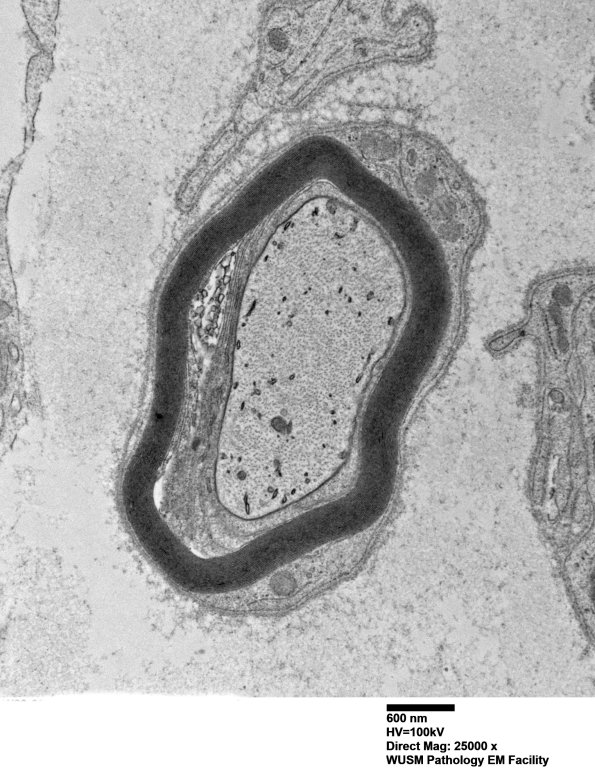

1C3A,B Another example of limited involvement in a case of established POEMS. (electron micrograph)